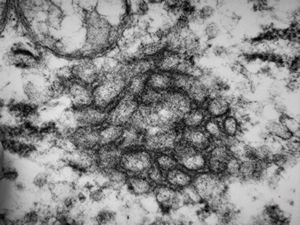

M,18y. | tubuloreticular complex in lymphocyte - unclassified hematologic disorder